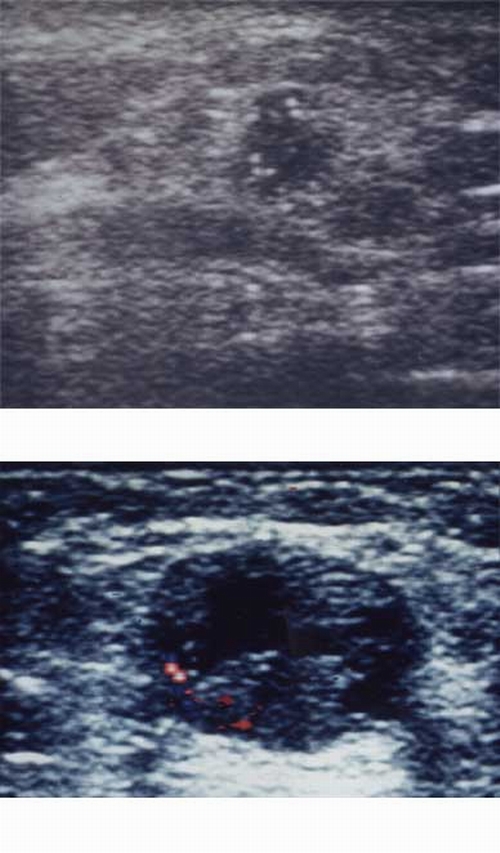

B. À¯¹æ ÃÊÀ½ÆÄ

À¯¹æ °ËÁø¿¡ÀÖ¾î ÃÊÀ½ÆÄÀÇ ¿ªÇÒÀº ¹°ÀÌ Â÷ ÀÖ´Â ³¶Á¾°ú ½ÇÁú µ¢¾î¸®(°íÇü Á¾±«)ÀÇ ±¸º° »Ó ¾Æ´Ï¶ó, À¯¹æ ÃÔ¿µ»ó µ¢¾î¸®(Á¾±«)ÀÇ

±¸ºÐÀ» ÇÒ ¼ö ¾ø´Â °æ¿ìµµ À¯¹æ³»ÀÇ µ¢¾î¸®(Á¾±«)¸¦ ã¾Æ³À´Ï´Ù. ±×·¯¹Ç·Î, ÃÊÀ½ÆÄ´Â ½ÇÁ¦·Î ¹°ÀÌ Â÷ÀÖ´Â ³¶Á¾°ú ½ÇÁú µ¢¾î¸®ÀÎ

°íÇü Á¾±«¸¦ ±¸ºÐÇϴµ¥ °¡Àå ÁÁÀº °Ë»ç ¹æ¹ýÀÔ´Ï´Ù.

½ÇÁ¦·Î ¿ì¸®³ª¶ó ¿©¼ºÀÇ °æ¿ì À¯¹æ ½ÇÁúÀÌ ¹ß´ÞÇÏ¿© À¯¹æ ÃÔ¿µ¼úÀÇ »çÁø»ó À¯¹æÀÌ ÀüºÎ ÇϾé°Ô º¸¿© ³¶Á¾À̳ª Á¾±« µîÀ»

ãÀ» ¼ö ¾ø½À´Ï´Ù. ±×·¯¹Ç·Î, ÃÊÀ½ÆÄ °Ë»ç¸¦ °°ÀÌ ½ÃÇàÇÏ¿©¾ß ÇÒ °æ¿ì°¡ ¸¹½À´Ï´Ù.